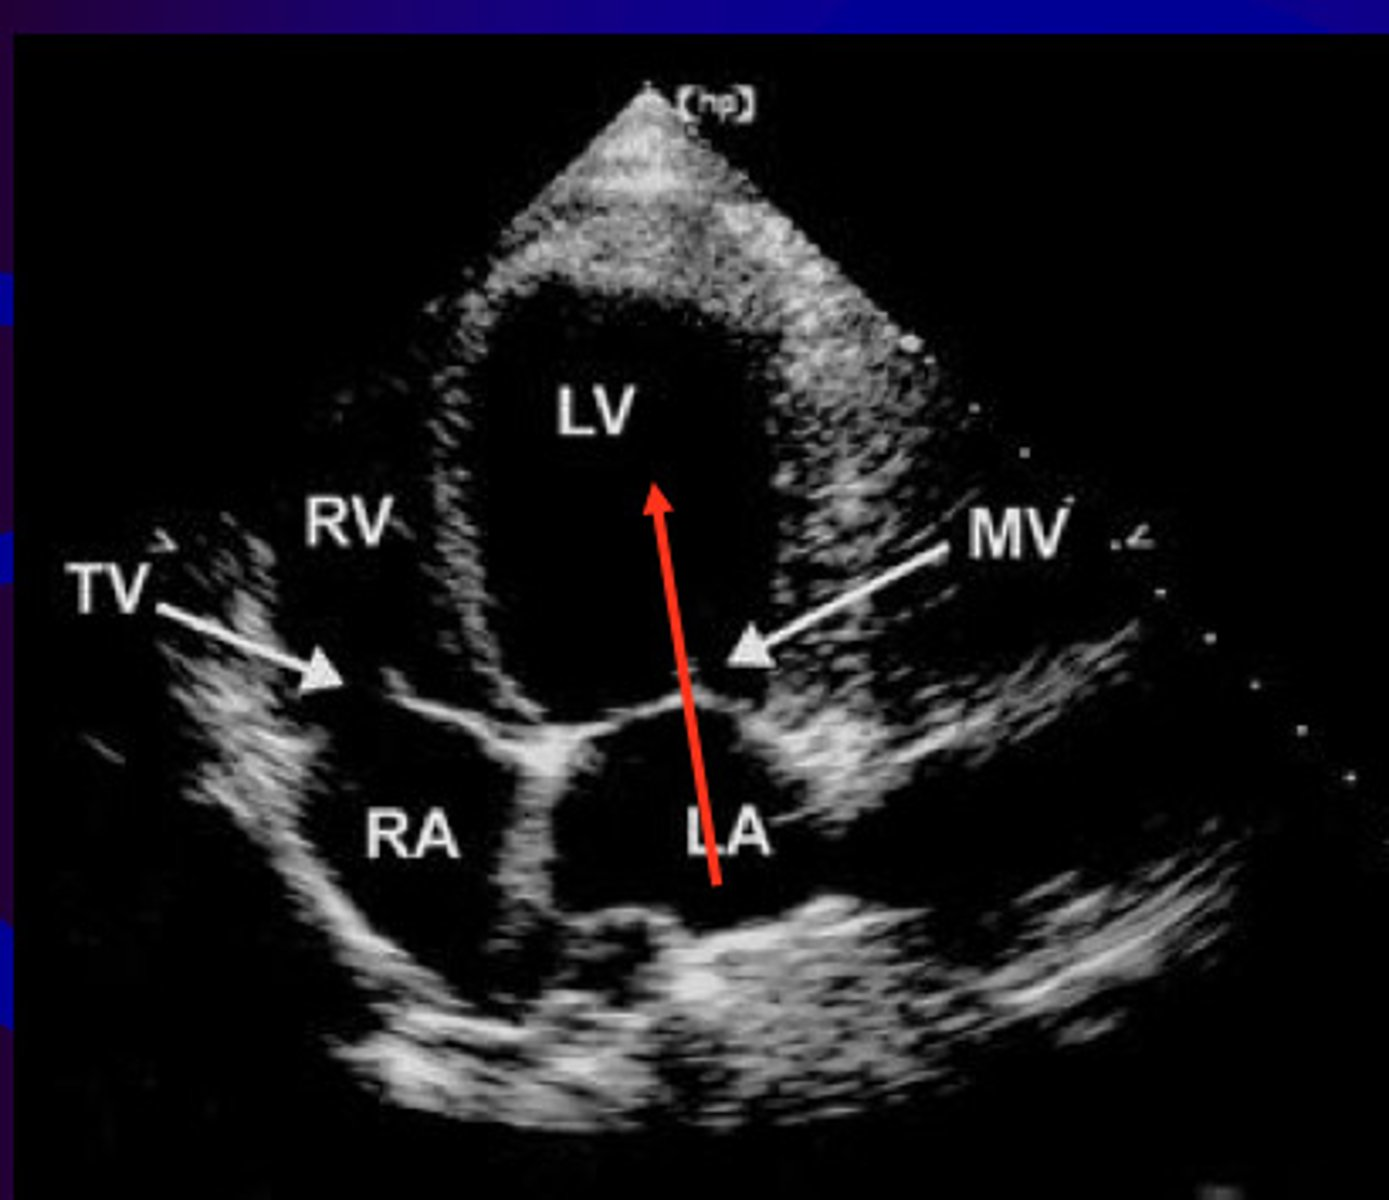

A4 is used to visualize _____ and ____

MV, TV

subcostal 4 is used to visualize _______, ___, ___, ____, and ___

four chambers, TV, MV, IVS, IAS